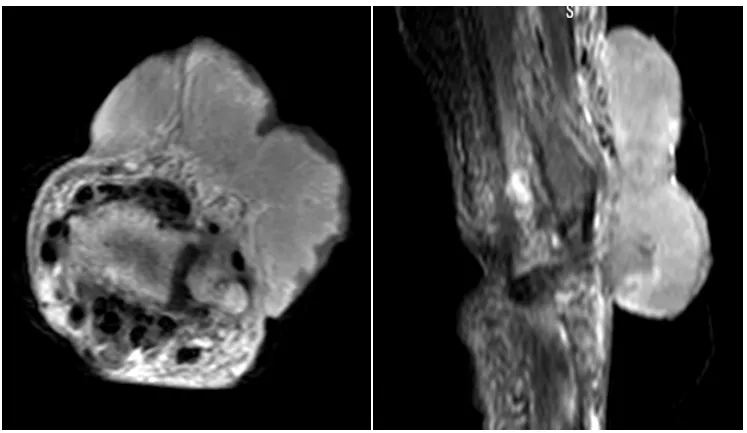

面对这位特殊患者,平度市人民医院肿瘤科医师团队第一时间联合当日坐诊的北京专家,共同细致查阅患者病历与影像资料,询问病史细节。考虑到老人91岁的高龄,手术不仅面临高风险,且肿瘤体积大导致切除难度极高,术后恢复周期长,再加上患者本身对手术强烈抵触,团队决定启动多学科会诊—— 邀请肿瘤专家、放疗专家、骨关节专家、影像专家等共同研判病情。

治疗阶段,专家们先通过穿刺明确病理诊断,确定肿瘤类型为中分化鳞状细胞癌。结合患者身体状况,精准勾画放疗靶区,反复优化放射治疗计划,在确保疗效的同时,为最大限度降低放疗副作用,保障患者安全,采用调强放疗技术实施治疗,治疗期间,医护人员时刻密切监测老人的生命体征与病情变化,及时给予对症支持治疗,确保放疗全程平稳推进。